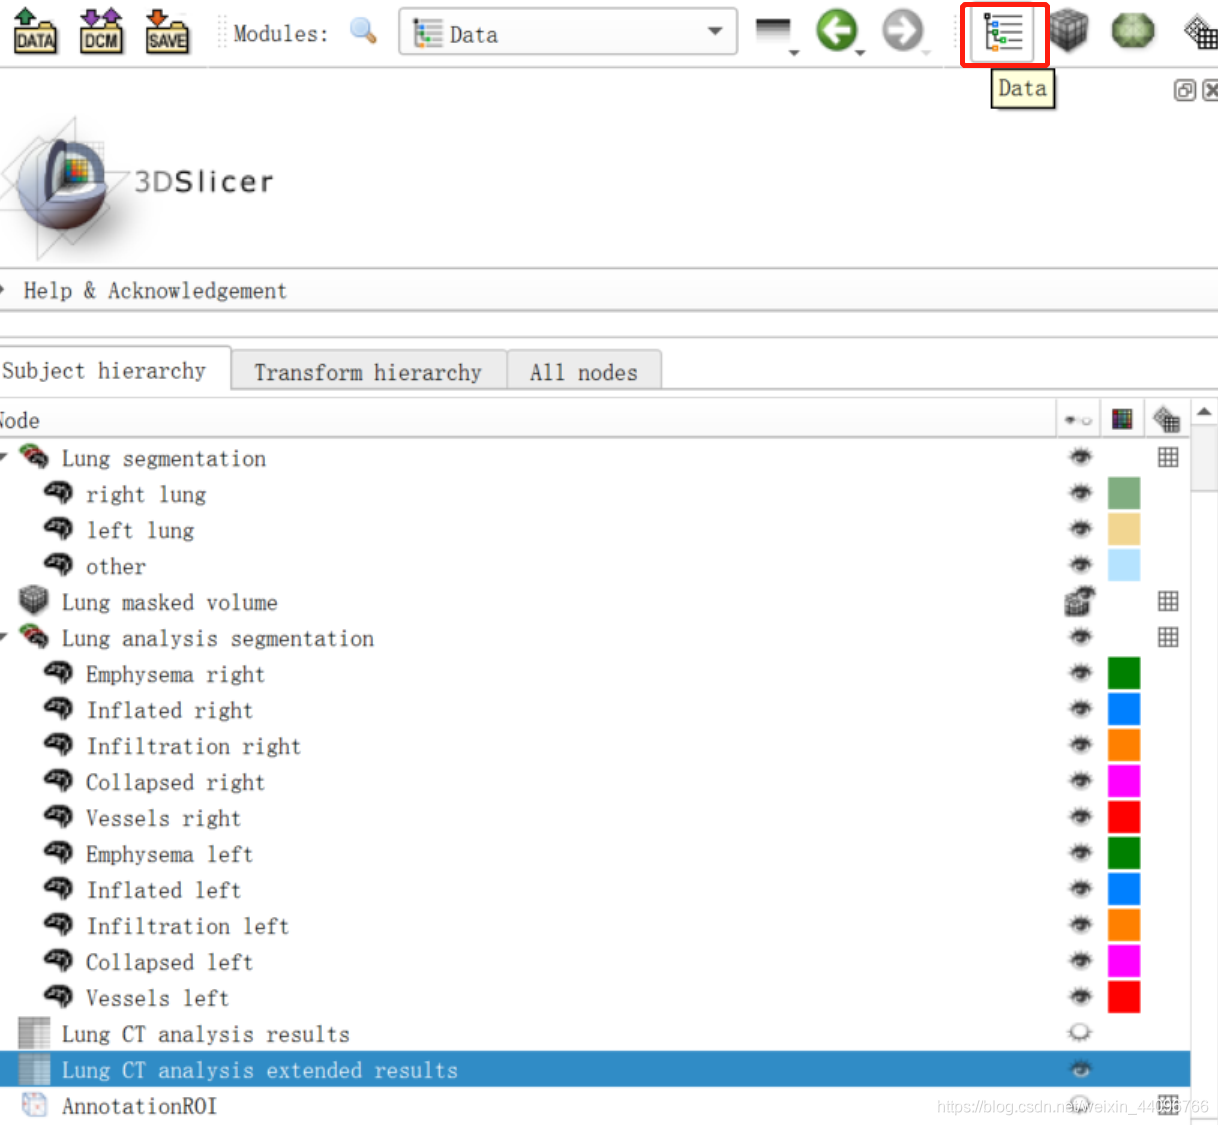

肺部分割

- 进入插件

- 点击start,根据提示在左、右肺、气管处标点后点击apply

分割出来的区域可以根据需要在Segment Editor中手动调整。

测量容积

- 进入插件

此处会弹出Error,直接点击ok即可。 - 设定阈值

阈值分割出肺大泡等病灶。

- 结果表

可以根据需要将表用不同格式导出。

注意:表中 Affected = Infiltrated + Collapsed

- show preview in 3D 查看3d效果

查看所有数据